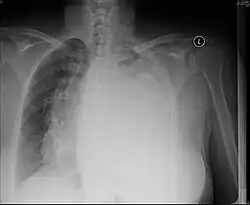

Masses

Masses such as tumors can also cause compression and displacement of mediastinal structures. There are various mediastinal tumors, and they are classified by their location in the chest. Notable examples include germ cell tumors and lymphomas.[12] Teratomas are a class of germ cell tumors that arise in the chest due to failure of germ cell migration during development. They can expand to large sizes and cause hemoptysis and pleural effusion. Radiographic features of teratomas typically include fluid and fat but also muscle, teeth, and bones inside the mass.[13]